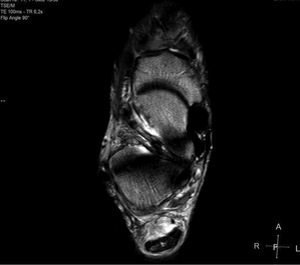

Pacjent, lat 52, zgłosił się do lekarza ortopedy z powodu silnego bólu w okolicy prawej pięty, który wystąpił nagle poprzedniego dnia podczas treningu piłki nożnej. Pacjent uprawia sport regularnie. Do tej pory nie cierpiał z powodu żadnych dolegliwości bólowych tej okolicy, a początek bólu nie był związany z bezpośrednim urazem. Podczas badania stopy okolica ścięgna Achillesa (piętowego) była obrzęknięta i bolesna, ruchy czynne w stawie skokowym znacznie ograniczone. Stwierdzono brak palpacyjnej bolesności w okolicy kostki przyśrodkowej i bocznej z zachowaną stabilnością w ruchach na boki.

Obrzęknięta okolica ścięgna Achillesa wraz z nagłym początkiem dolegliwości wskazuje na jego zerwanie. Niemniej możliwość wykonywania czynnych ruchów w stawie skokowym, nawet w niewielkim zakresie, przemawia za innym rozpoznaniem. Nie występuje też wyczuwalna luka w ścięgnie, jednak może być ona maskowana obrzękiem tej okolicy. Zapalenie kaletki głębokiej ścięgna Achillesa również może wywołać podobne objawy. Często wiąże się ono z występowaniem wyrośli kostnej na kości piętowej (deformacja Haglunda), która drażniąc kaletkę, wywołuje jej stan zapalny. Do złamań zmęczeniowych kości piętowej najczęściej dochodzi u żołnierzy oraz sportowców, którzy biegają długie dystanse po twardym podłożu. Jednakże w tym wypadku jest to mało prawdopodobne rozpoznanie, ponieważ pacjent może stanąć na pięcie oraz nie ma krwiaka i obrzęku tej okolicy.